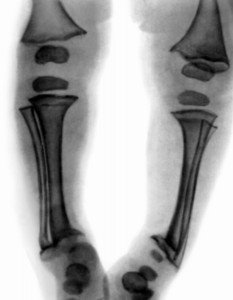

РахитизмОб этой заболевания знали ещё в  древней Европе. Приблизительно к 16 веку рахитизм стал довольно распространённой заболеванием посреди малышей.  Не случаем таланты тех пор (живописцы)  старались изобразить «суровую действительность», а конкретно таких малышей. Но эти времена прошли, неуж-то и в наше время случаются случаи существования таких малышей? И на данный момент это болезнь всераспространено, и вновь оно касается  категории «маленькие дети».  Что все-таки такое рахит?

Это нарушения, которые появились в организме малеханького ребёнка, они затронули нервную и костную системы. Это, во-1-х, а во вторых задели всех других органов и систем ребёнка. Мы на данный момент говорим о «настоящем рахите» либо человеке, который находится в зависимости от витамина D. Конкретно нехватка этого витамина приводит, к возникновению у малышей рахитизма. У пенсионеров она проявляется в виде остеопороза и остеомиляции.